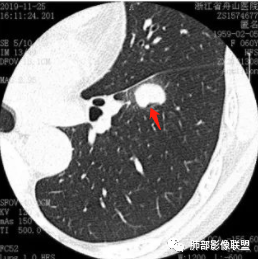

这个病例看上去像个爱心,但是具备恶性征象不少,有分叶,脐凹,支气管截断,膨隆,月牙铲等。没有毛刺,牵拉力不强,多见于低分化肿瘤,其收缩力可以消失,特别是实体型。实体型内部纤维组织很少。与不典型类癌鉴别比较难,典型类癌分叶不明显;不典型类癌男女比例差不多,少见。

图一:提示支气管截断;图二:看到脐凹血管进入;图三:月牙铲;图四:典型分叶;图五:病灶膨隆,图六:支气管截断可能。 医学百科网 | YxBaike.Com